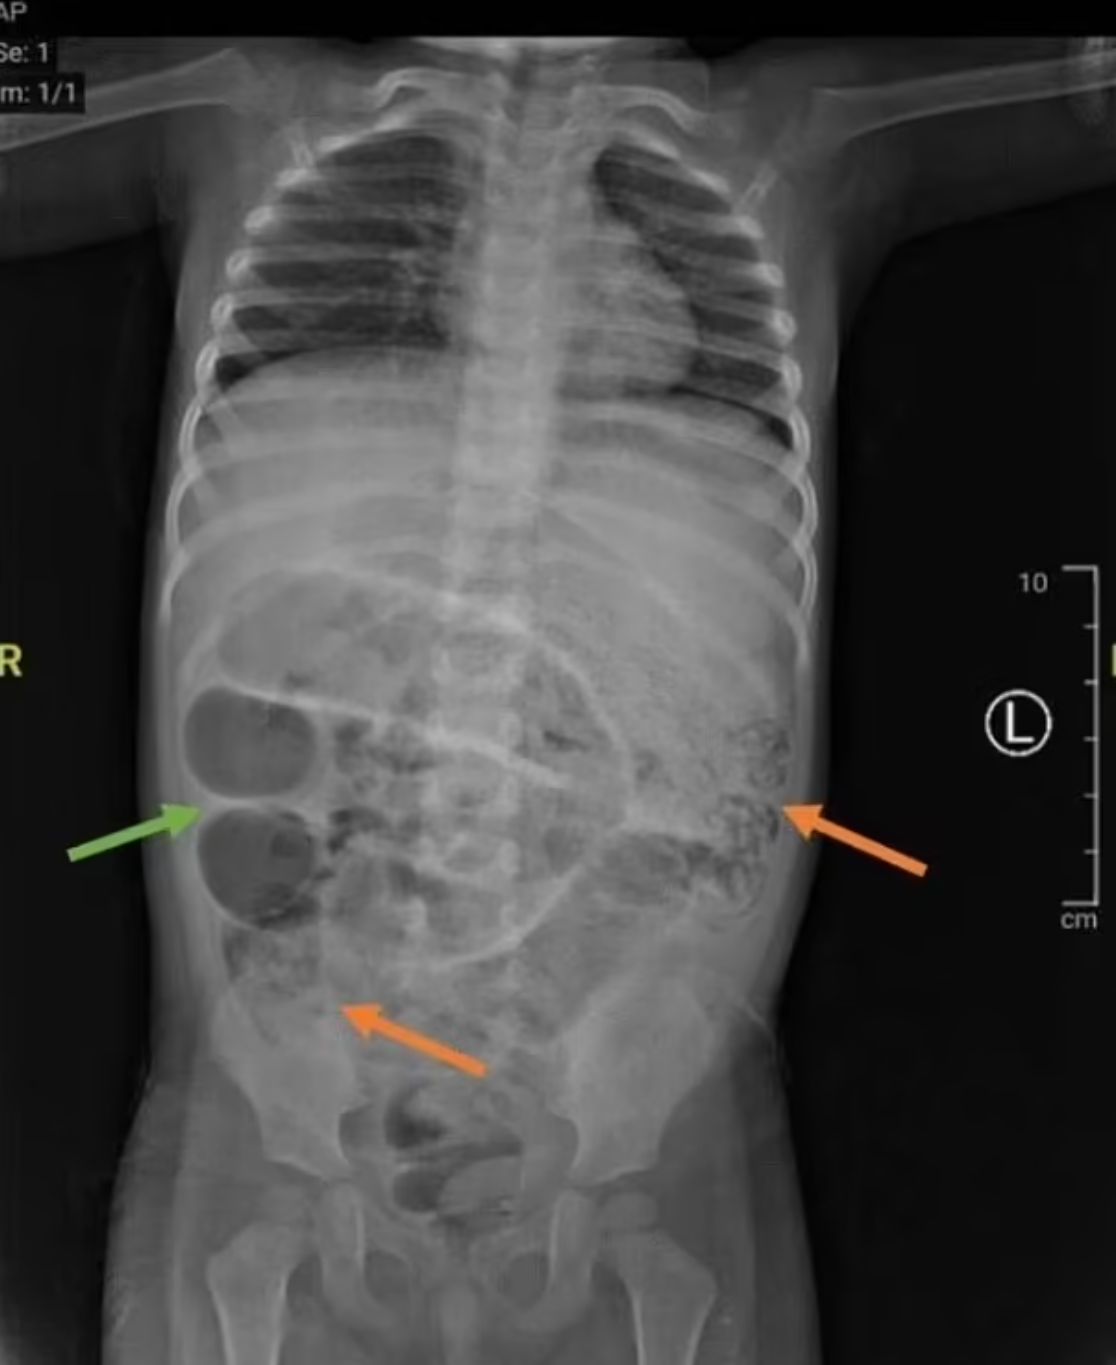

【寄生蟲/蛔蟲/感染/腹脹/發燒/排便/蠕蟲】綜合外媒報道,據印尼醫生在期刊中分享的病例,當地一名3歲男童出現腹脹、發燒和3天未能排便送院,最初被診斷為便秘。然而,1天後他開始吐出蛔蟲,隨後的腹部X光顯示出灰色的團塊,顯示他出現腸梗塞。

醫生為他進行剖腹手術,發現蛔蟲阻塞其小腸3個不同部位。這種蛔蟲可長達35厘米,並且能在人體內生存。